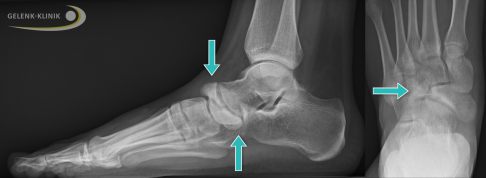

Röntgenbild seitlich: Im späten Stadium des Müller-Weiss-Syndroms sind das Fersenbein (Calcaneus) und das Fußlängsgewölbe abgesunken. Im Kreis ist das nach oben heraustretende Knochenstück des Kahnbeins sichtbar. Die Schädigung betrifft bereits das nachfolgende Gelenk zwischen Kahnbein und Keilbein. © Gelenk-Klinik

Die fortschreitende Schädigung des Kahnbeins an seiner Außenseite (lateral) führt zu einer keilförmigen Formänderung des Knochens. Im Verlauf der Müller-Weiss-Erkrankung erscheint das Fußlängsgewölbes zunächst erhöht, um dann deutlich abzusinken. Es droht sogar ein kompletter Kollaps des inneren Fußgewölbes.

Mit dem Fortschreiten der Erkrankung ändert sich Stellung des Sprungbeins (Talus) und damit auch die Stellung des Rückfußes im Verhältnis zum Vorfuß. Üblicherweise sinkt der Sprungbeinkopf (der vordere Anteil des Talus) nach unten außen ab. Schließlich kann das defekte Kahnbein auseinanderbrechen und ein großer innerer und ein kleiner äußerer Knochenteil entsteht. Die Bruchstücke verschieben sich charakteristisch: Der innere Knochenteil tritt nach unten innen und wölbt den inneren Fußrand vor. Der äußere Knochenteil wandert nach oben außen und wird dort prominent. Schließlich tritt das Sprungbein mit den drei Keilbeinen (Os cuneiforme) in Kontakt, das zerbrochene Kahnbein hat keine funktionierende Gelenkfläche mehr.

Die Röntgenaufnahmen zeigen bei fortgeschrittenem Müller-Weiss-Syndrom ein abgeflachtes Kahnbein, dass zunehmend nach innen (medial) und Richtung Fußrücken (dorsal) verdrängt wird. Das Kahnbein kann wie ein Komma erscheinen. Durch den Umbau (Sklerosierung) des abgestorbenen Knochenbereichs erscheint das Kahnbein auf der Röntgenaufnahme deutlich dichter und kompakter. In frühen Stadien der Erkrankung ist die Röntgenuntersuchung nicht hilfreich, da die knöchernen Veränderungen noch nicht sichtbar sind.